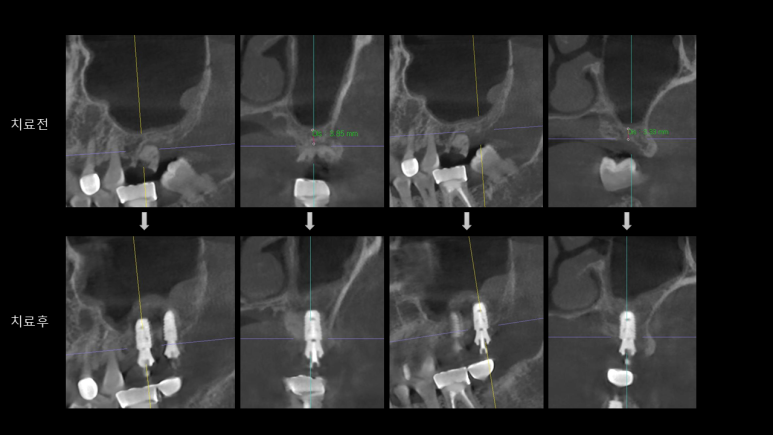

🦷 치료 대상: 상악 제1·2대구치 부위

| 상악 제 1대구치 | 상악 제 2대구치 |

CT 촬영 결과,

해당 부위는 골 높이 3~5mm 수준으로,

단순 식립만으로는 충분한 고정력을 확보하기 어려웠습니다.

다행히도:

- 상악동 점막이 건강하고

- 바닥(저부) 형태가 평탄하여

잇몸을 크게 절개하지 않는 수압 거상술로 접근하였습니다.

📸 수술 3개월 후 예후

- CT 상 점막 상태 양호

- 이식한 골 형성도 안정적으로 진행

- ISQ 수치(고정력 지표)도 정상 수치 도달

→ 예후가 매우 좋았습니다 😊